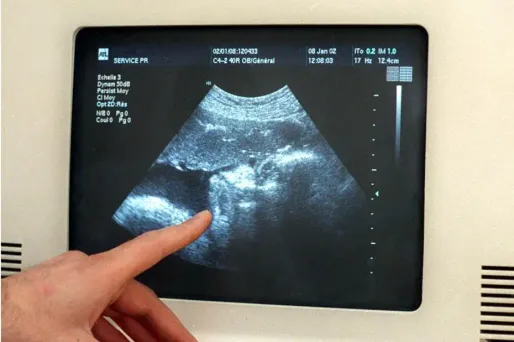

Une échographie (photo d'illustration).

Une échographie (photo d'illustration). © MAX PPP